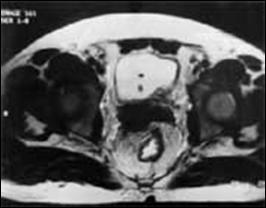

2. Diagnosticul diferential cu ureterocel bilateral